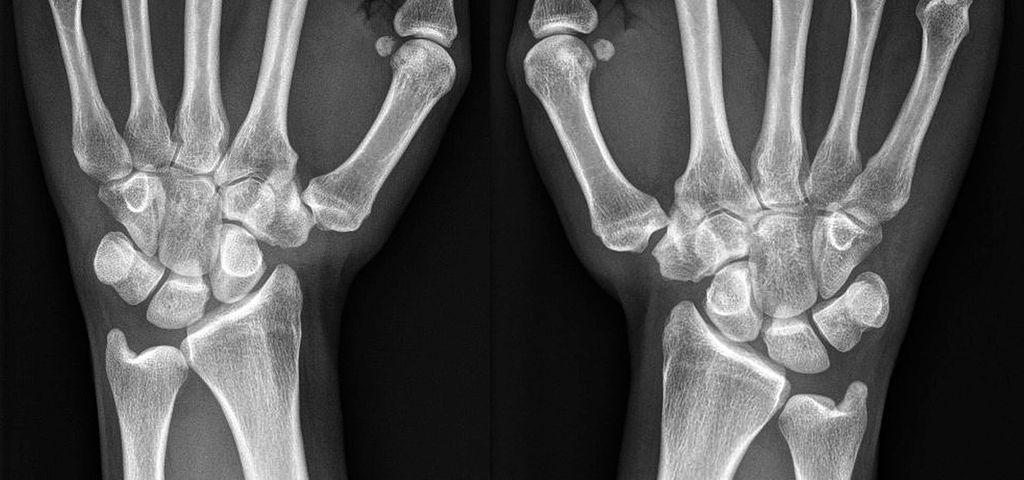

Abb. 1: Handgelenksröntgen einer 16-jährigen Patientin mit schmerzhafter CMC1-Instabilität rechts und deutlicher Trapeziumhypoplasie beidseits

Die Ursachen einer Instabilität sind mannigfaltig. Eine traumatische Luxation des CMC1-Gelenkes ist aufgrund des kräftigen Kapselbandapparates selten, jedoch kann eine axiale Krafteinwirkung auf die flektierte Basis des Mittelhandknochens des Daumens zu einem Riss der dorsalen Kapsel führen und somit eine (Sub-)Luxation verursachen.2 Eine Verletzung des dorsoradialen Ligaments dürfte dabei biomechanisch für traumatische Instabilitäten des CMC1-Gelenkes ausschlaggebend sein.6,7 Aufgrund der kräftigeren palmaren Gelenkskapsel ist diese Verletzung oft von Avulsionsfrakturen an der Basis des Mittelhandknochens begleitet.2 Weitere Ursachen einer Instabilität im CMC1-Gelenk sind idiopathische oder hormonell bedingte Bandlaxizitäten, genetische Prädisposition, insbesondere bei Kollagenmutationen (z.B. Ehlers-Danlos-Syndrom), oder repetitive Tätigkeiten mit Überbeanspruchung.8 Abnormale Gelenksflächen, z.B. ein erhöhter Slope bei Dysplasien des Trapeziums (siehe Abb. 1), führen zu einer Überbeanspruchung der Bänder und können Instabilitäten aggravieren.9,10